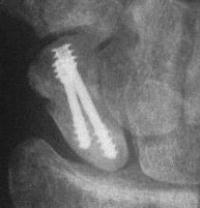

and healing.

Click for larger image